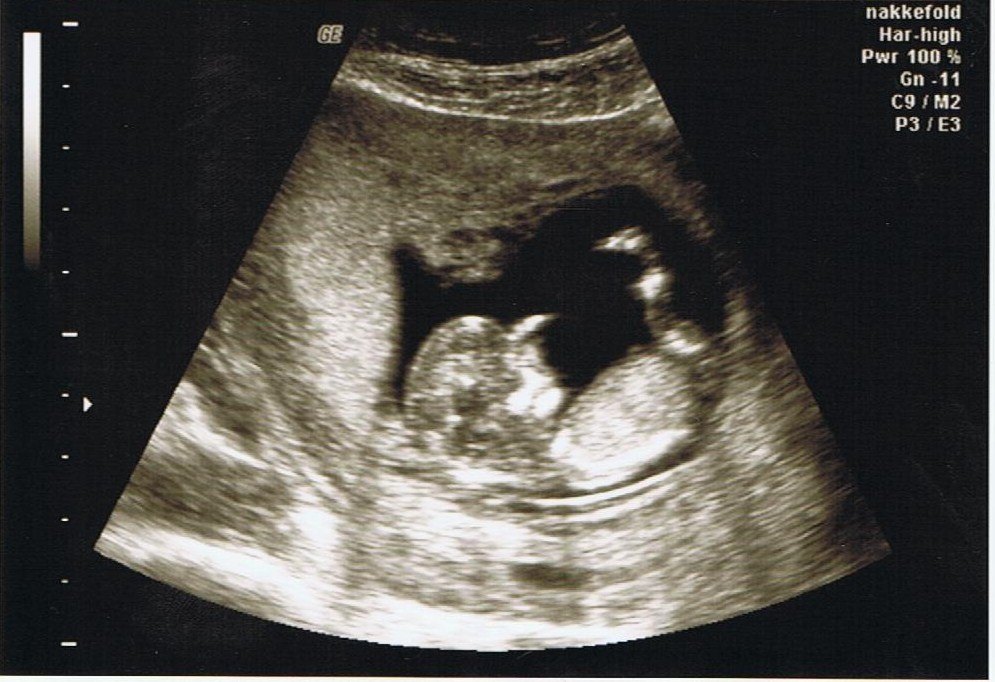

Så kom den længeventende dag, dagen hvor jeg skulle scannes. Jeg har bare været rigtig rigtig nervøs idet jeg opdagede et dødt foster sidst jeg blev scannet ved en nf. Men denne gang gik det bare SÅ godt

Den dansede og spralede som bare pokker derinde...Smukt

Så nu ser jeg frem til den 8 november hvor jeg skal til md - scanning. Jeg blev sat en uge tilbage, men hvad gør det når milepælen ER nået, 12+2

doubletesten + scanningen viste et tal på godt 5600 som skulle være helt perfekt.

Et lille billede til jer